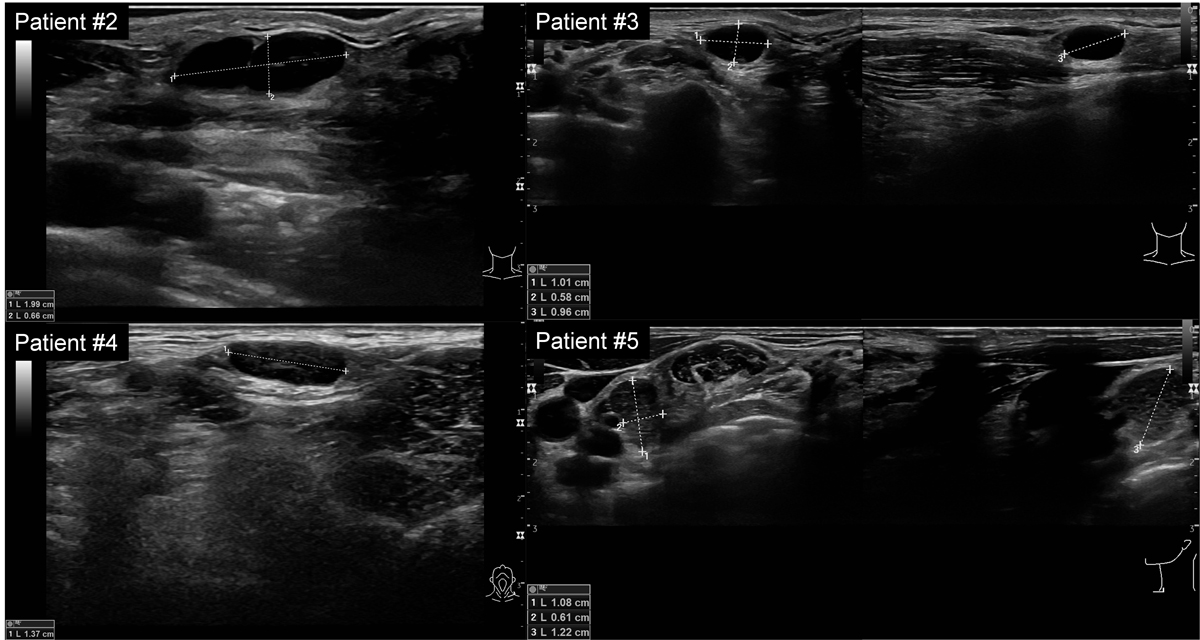

All patients presented with palpable or easily detectable superficial lymph nodes on ultrasound in different locations, either in cervical level IV, supra-, infra-, or retroclavicular regions, and in the axilla. Sonographic imaging revealed partially hypo- and partially isoechogenic lymph nodes (fig. 1A). The width ranged from 1.0 to 2.4 cm in size, with ovoid to rounded shapes, sharp borders and only partially detectable hilum. Some lymph nodes presented with suspicious sonographic findings (spherical shape with loss of hilum) [25] (see also supplementary fig. S2 in the appendix).

Figure S2 Ultrasound findings of Patients 2–4 showing enlarged ovoid to spherical lymph nodes with loss of hilum.